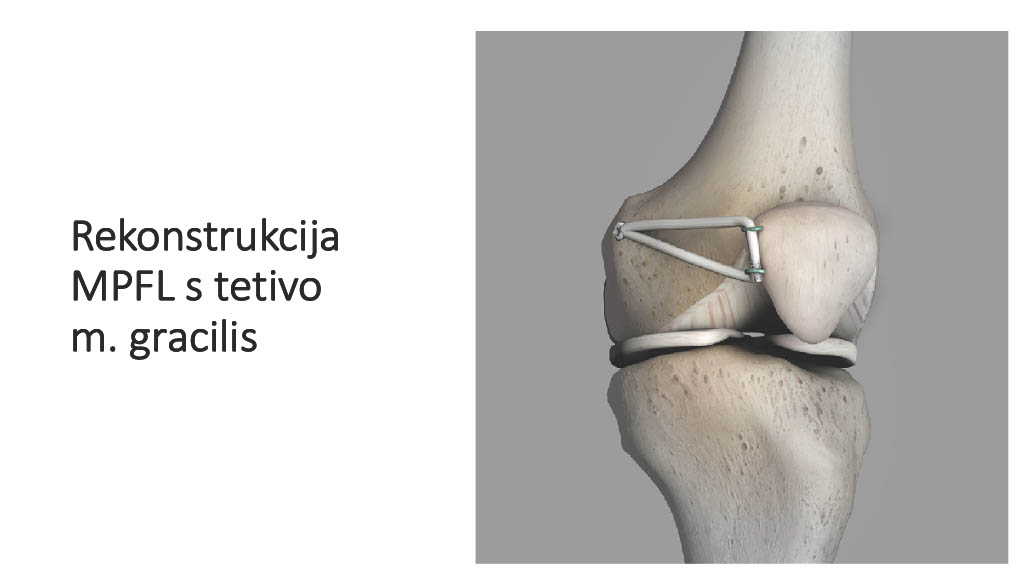

Vogrin, Matjaž, MD, PhD.

Department of Orthopaedics & Sports Medicine Institute, University Medical Centre Maribor, Slovenia

“Surgical treatment of knee injuries in skiing”

Prof. Matjaž Vogrin is an orthopaedic surgeon and specialist in arthroscopic surgery and sports injuries. He is chairman of the Institute of Sports Medicine ” at the Faculty of Medicine in Maribor, Slovenia, and head of the medical subdivision of the Slovenian National Olympic Committee.

He was chief physician of the Slovenian Olympic team at the 2012, 2016, 2021 and 2024 Olympic Games (London, Rio, Tokyo, Paris), official physician of the Slovenian national football team and head of the Slovenian medical team at the 2010 FIFA World Cup in South Africa. He has also been head of the medical team of FC Maribor ( UEFA Champions League and Europa League participants) since 1999. He has been an invited speaker at sports medicine congresses and conferences worldwide.

Surgical treatment of knee injuries in skiing